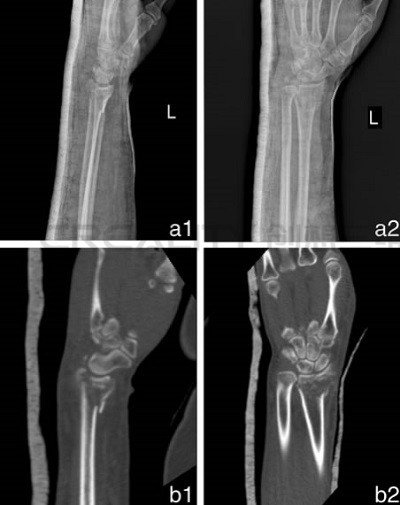

3D打印機(jī)制造模型如何改善骨折治療

中國研究人員正在研究使用3D打印機(jī)制造模型來改善骨折治療。第二附屬醫(yī)院骨科和浙江溫州醫(yī)科大學(xué)育英兒童醫(yī)院的華晨在“使用3D打印機(jī)制造的模型來改善骨折治療功效&rd...